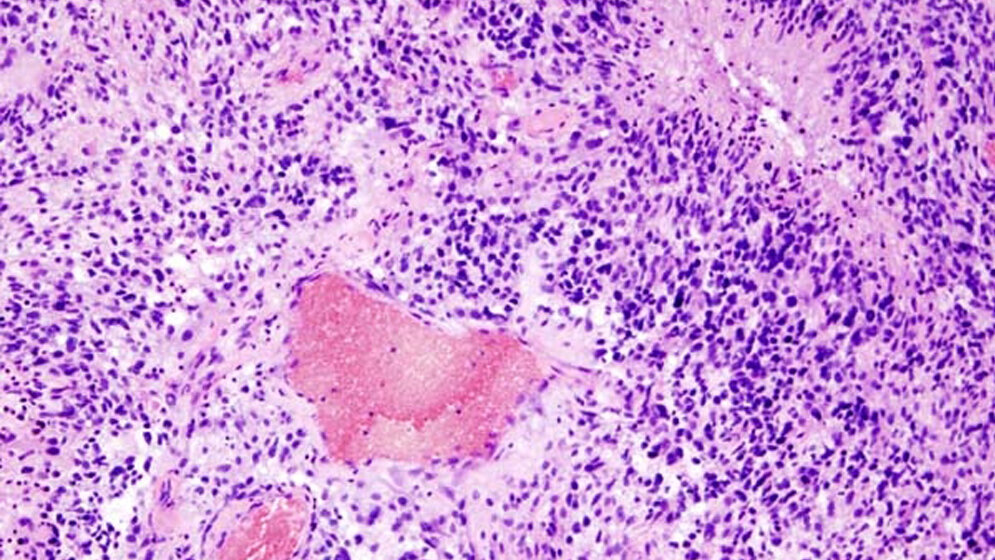

Um die molekulargenetischen Eigenschaften eines Tumors zu charakterisieren, müssen Ärzte dem Patienten eine Gewebeprobe entnehmen, also eine Biopsie oder Operation durchführen. Von der genetischen Ausstattung eines Tumors kann dann auch abhängen, welche Behandlungsschritte – vor allem Strahlen- und Chemotherapie – ergänzt werden müssen.